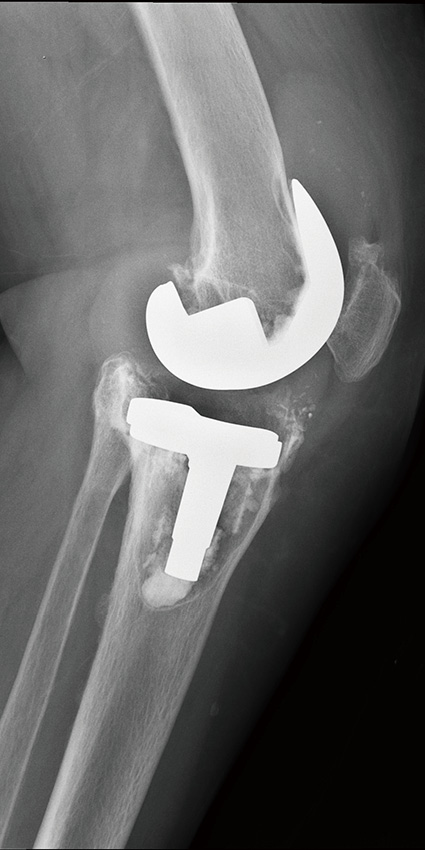

单髁膝关节置换术后8年,塌陷,接受全膝关节表面置换术

单髁置换

膝关节内侧间隙狭窄,适合单髁置换,手术后恢复快,

关节活动最大限度保留